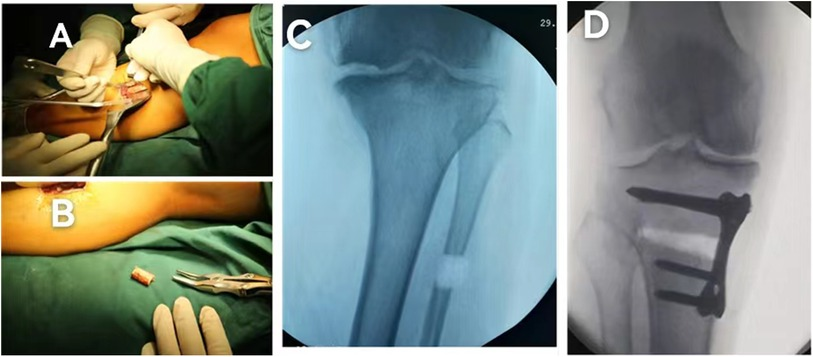

HOT ! 大腿骨近位部骨折 Surgical technique 大腿骨近位部骨折:大腿骨頚部・転子部・転子下骨折の手術手技

大腿骨近位部骨折 Surgical technique 大腿骨近位部骨折:大腿骨頚部・転子部・転子下骨折の手術手技の詳細情報

大腿骨近位部骨折:大腿骨頚部・転子部・転子下骨折の手術手技。高齢者大腿骨近位部骨折 - 東京科学大学 整形外科。Frontiers | A new technique of autologous bone grafting for。こちらの商品は裁断機にて裁断済です。顔貌・骨格・顎関節から導く 機能的顔貌主導型インプラント治療。裁断されてバラバラの状態であることを御理解の上ご購入をお願いいたします。獣医内科学 第3版 伴侶動物編。裁断済みのため全体的に状態が悪いとしています。【裁断済み】新核医学テキスト。確認した限り書き込みやマーカーはありません。日本語版 正規品★トーキングトゥヘブン☆ミディアムシップカード★オラクルカード。サージカルテクニック 大腿骨近位部骨折大腿骨近位部骨折の手術手技を詳細に解説した専門書。助産学講座 助産師 教科書。- タイトル: 大腿骨近位部骨折- サブタイトル: Osteosynthesis & Arthroplasty- 著者: 高橋裕治, 上原秀樹, 神田健二, 北田貴則- ジャンル: 外傷整形外科ご覧いただきありがとうございます。歯科衛生学シリーズ 歯科予防処置論・歯科保健指導論。

• 大腿骨近位部骨折:大腿骨頚部・転子部・転子下骨折の手術手技